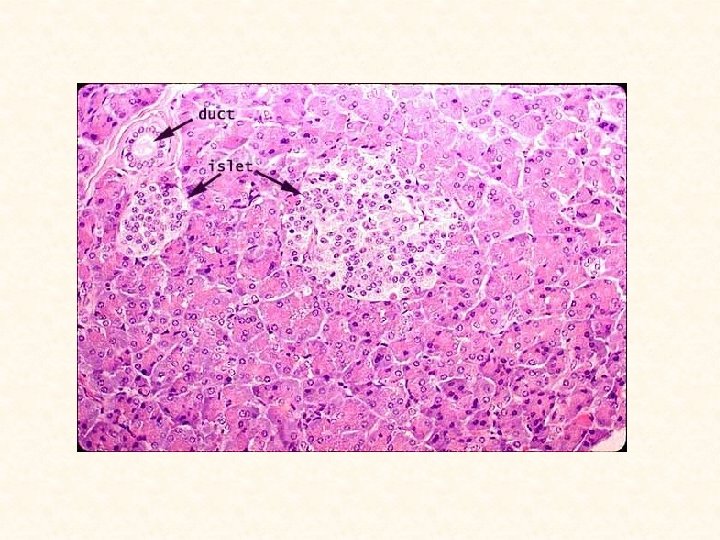

Pancreas (endocrine) B. Islets of Langerhans (endocrine pancreas): • Richly vascularized clusters (100 -200 µm diameter) of endocrine cells surrounded by fine network of reticular fibers. • Scattered among acini of exocrine pancreas in random fashion. 1. Islet cells: a. Differentiated from each other by immunocytochemistry or special stains. b. Produce several polypeptide hormones, each cell type produces only one hormone.

Pancreas Figure 1 : Pancreas -Has both exocrine and endocrine components. -Exocrine portion is bulk of organ: compound tubuloaveolar gland, secreting serous fluid. -Gland subdivided into lobules by connective tissue septa (CT). -Each acinus (Ac) made of several pyramid-shaped cells, with round nuclei. - Endocrine portion is small, spherical clumps of cells, islets of Langerhans (IL). -Cells located in center of acinus: centroacinar cells (CA). Figure 2: Pancreas Figure 3: Pancreas Figure 4: Islets of Langerhans -Higher mag. of Figure 1. -Connective tissue septa (CT), -Trapezoidal morphologies of individual cells of serous acini (arrow). -Centroacinar cells (CA), located in center of acini. -Pancreatic acinus look like a pie, with individual cells clearly delineated (arrows). -Nucleus (N) of each trapezoid-shaped cell is round and basal cytoplasm (arrowhead) homogeneous. -Apical cytoplasm packed with zymogen granules (ZG). -Centroacinar cells (CA) recognized by their locations as well as by pale appearance of nuclei. -Islets of Langerhans (IL), serousacini (Ac), Blood supply (BV) -Connective tissue elements (CT) -Erythrocyte (RBC) -Although each islet is composed of A, B, C, and D cells, they can only be distinguished from each other by special stains.